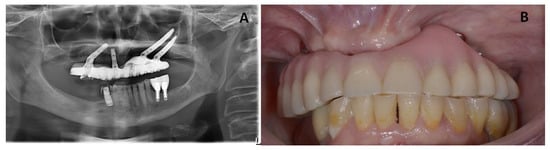

Initial visits of the patient in 2014. Maxillary site: The patient had an edentulous maxilla with two conventional implants in the region of #22 and #26 (tilted implant) and #12 and #16 (tilted implant) which were inserted in February 2014 as an anchorage for All-On-4 bridge in November 2014. Mandibular site: The patient also presented a partially edentulous lower jaw with seven natural teeth (#34, #33, #32, #31, #41, #42, and #43), and four conventional implants (#44, #46, #35, and #36) which were inserted in 2007, supporting two bilateral fixed bridge prostheses that were delivered for the renewal of prostheses for esthetic and functional reasons and for better occlusion in November 2014 (Figure 1).

Figure 1. (A) Radiographic image from the patient showing an MRONJ lesion on the posterior left side of the maxillary bone. (BD) Clinical images from the patient showing an MRONJ lesion on the posterior left side of the maxillary bone.